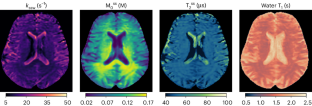

Deep learning-based saturation transfer magnetic resonance fingerprinting (MRF) is an emerging approach for noninvasive in vivo imaging of proteins, metabolites and pH. It involves a series of steps, including sample/participant preparation, image acquisition schedule design, biophysical model formulation and artificial intelligence and computational model training, followed by image acquisition, deep reconstruction and analysis. Saturation transfer-based molecular MRI has been slow to reach clinical maturity and adoption for clinical practice due to its technical complexity, semi-quantitative contrast-weighted nature and long scan times needed for the extraction of quantitative molecular biomarkers. Deep MRF provides solutions to these challenges by providing a quantitative and rapid framework for extracting biologically and clinically meaningful molecular information. Here we define a complete protocol for quantitative molecular MRI using deep MRF. We describe in vitro sample preparation and animal and human scan considerations, and provide intuition behind the acquisition protocol design and optimization of chemical exchange saturation transfer (CEST) and semi-solid magnetization transfer (MT) quantitative imaging. We then extensively describe the building blocks for several artificial intelligence models and demonstrate their performance for different applications, including cancer monitoring, brain myelin imaging and pH quantification. Finally, we provide guidelines to further modify and expand the pipeline for imaging a variety of other pathologies (such as neurodegeneration, stroke and cardiac disease), accompanied by the related open-source code and sample data. The procedure takes between 48 min (for two proton pools or in vitro imaging) and 57 h (for complex multi-proton pool in vivo imaging) to complete and is suitable for graduate student-level users.

Perlman, O., Farrar, C. T. & Heo, H.-Y. MR fingerprinting for semisolid magnetization transfer and chemical exchange saturation transfer quantification. NMR Biomed. 36, e4710 (2023).